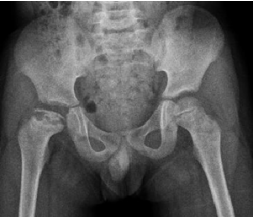

28 12 歲男童抱怨腿痛已六個月,其 X 光如圖所示,則最可能之診斷為何?

(A)派翠克氏病(Patrick) (B)帕氏病(Perthes) (C)佩杰氏病(Paget) (D)髖關節半脫位